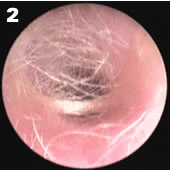

小婴儿耳道有丰富的绒毛,有时会影响窥视